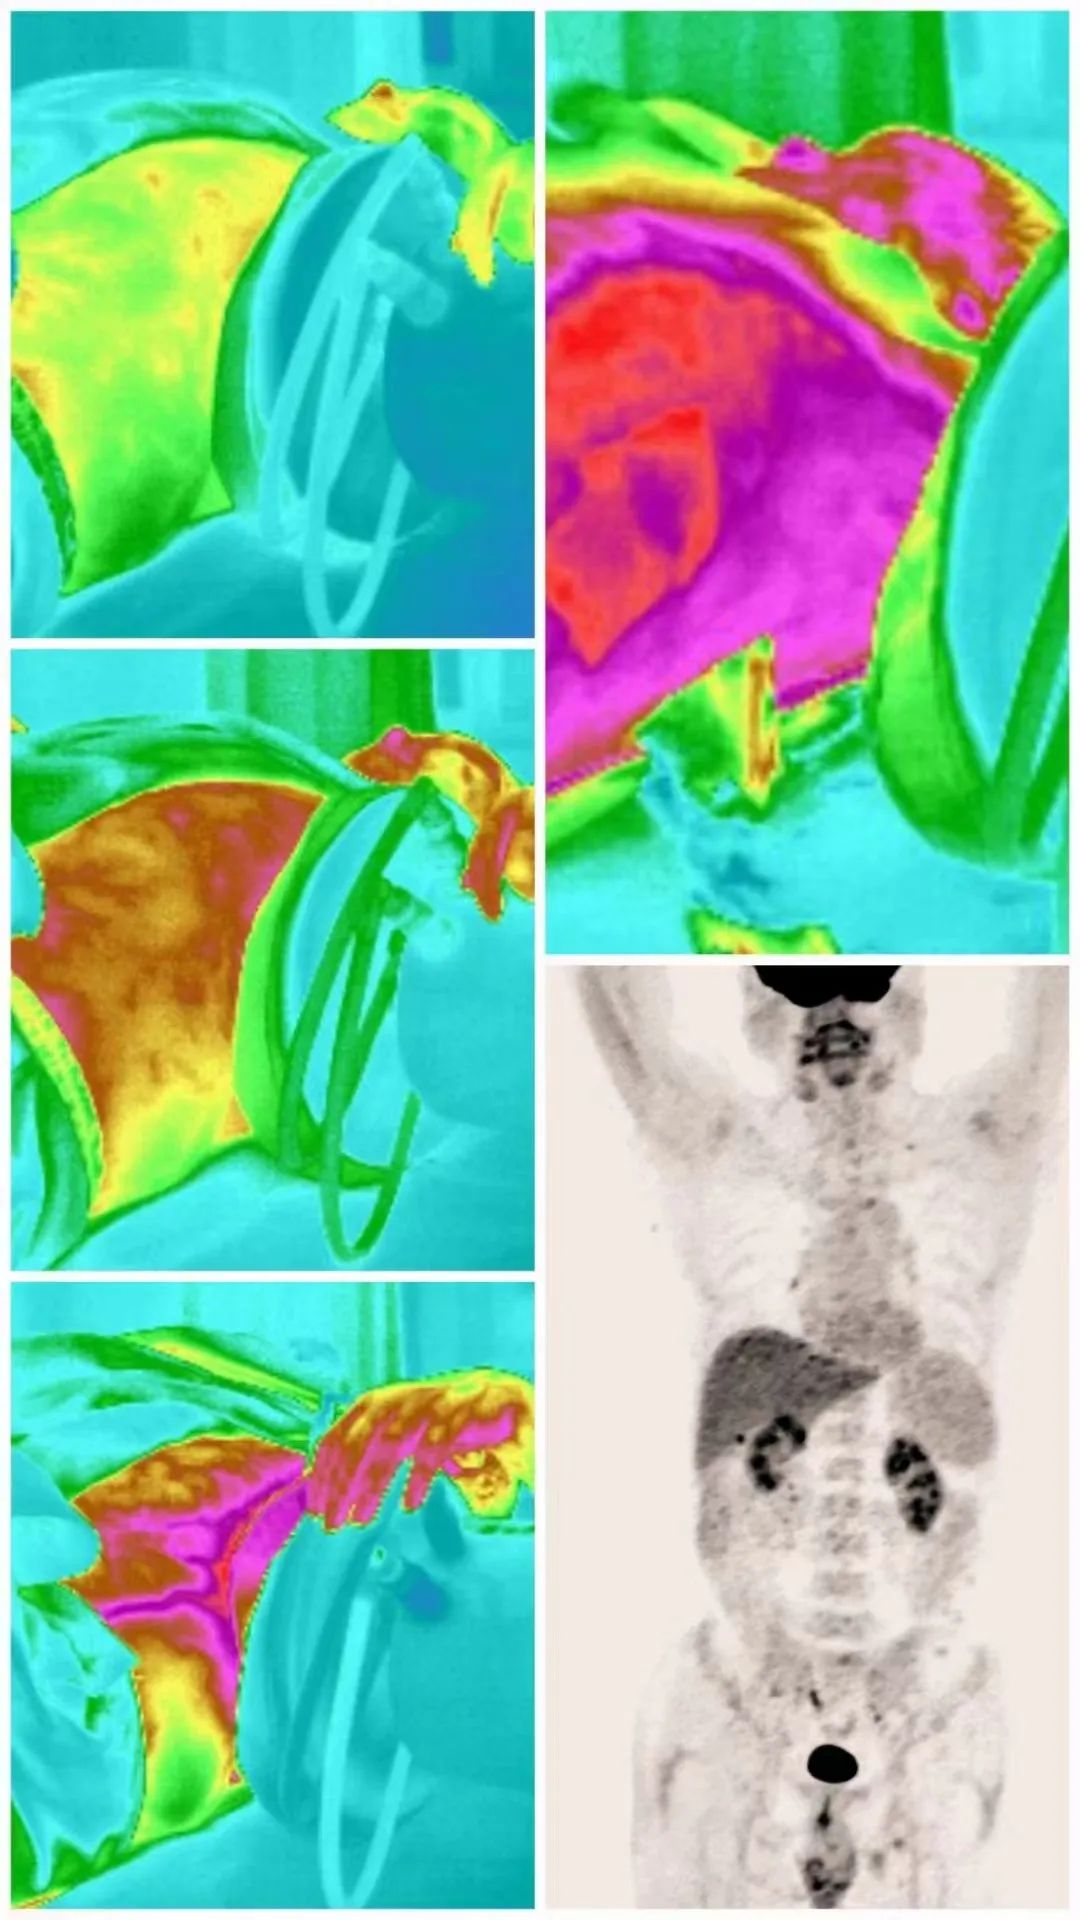

Case Review

Case 1: Patient with liver metastasis from renal cell carcinoma underwent immunotherapy for 2 years and received a total of 55 combined sessions of hyperthermia. Currently, imaging shows the disappearance of tumors, tumor markers have decreased to normal levels, and the patient’s weight has increased from 110 pounds to 145 pounds. They can lead a relatively normal life.

Case 2: Patient with pulmonary mucinous adenocarcinoma experienced disease progression after surgery, radiation therapy, targeted therapy, and immunotherapy. The cancer had widespread metastasis with pleural effusion. Increasing speed ion therapy combined with advanced immunotherapy was initiated three weeks ago. The treatment has shown no side effects, and the patient has no significant discomfort. This treatment represents the patient’s last chance.

Case 3: Postoperative colorectal cancer patient who had to discontinue targeted therapy due to severe skin damage. After completing one session of high-speed ion therapy, the patient gained 11 pounds in weight.